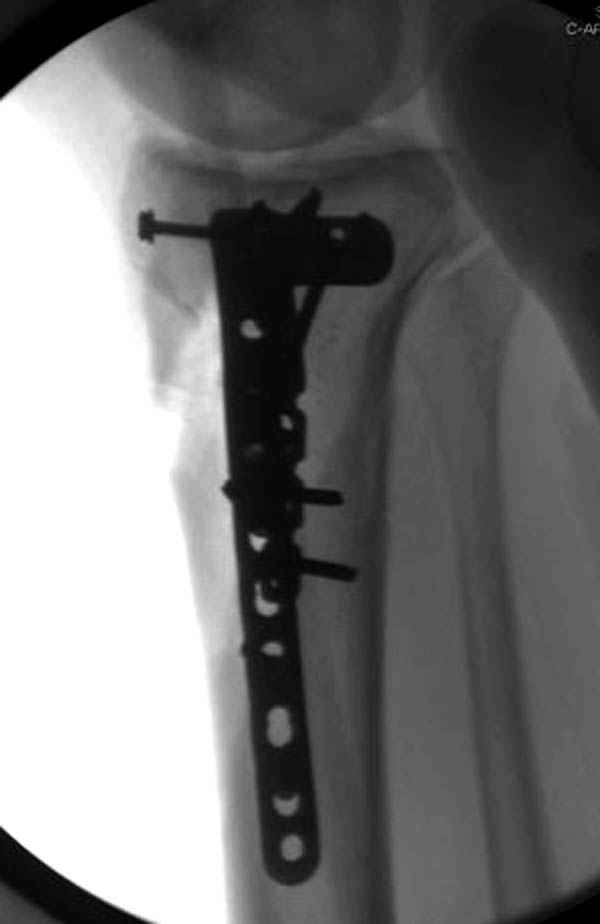

Уважаемые коллеги! В прошлую пятницу больной прооперирован - как и планировалось мыщелковая LCP от ChM. Малоинвазивно не получилось - один большой доступ :(. (но с минимальным скелетированием б/б кости). Наружный мыщелок собрали, но по контролю видно, что задне-медиальный отдел метаэпифиза смещен. Фиксировать не стали (?). 4-е сутки после операции - по м/тканям без проблем. Дополнительная иммобилизация синтетическим тутором.

P. S. перелом диафиза на контроле не совсем захвачен, но проблем там нет. Приношу извинения за низкое качество Р-грамм - выполнены на сканере (фотоаппарат не работает :)) .

Трудно поверить, что разрекламированная Ортопедическая школа Восточной Украины позволяет такие странные снимки? На прямом снимке сохранен общий контур плато, но не известна судьба импрессии суставной поверхности. На полубоковой?, оставлен без репозиции задне-медиальный отдел, и навряд ли после такой фиксации можно удовлетвориться результатом.

Такая ситуация характерна для многих, когда принимается ошибочное решение, т.е пытаются фиксировать одним имплантом переломы двух мыщелков. Латеральная пластина приемлема только для тех случаев, когда сохраняется интактным медиальный диафизарный кортекс и отсутствует фрагментация на верхушке медиального перелома.

Представленные снимки не информативны, нужны отдельные качественные снимки коленного сустава и голени без ротации.